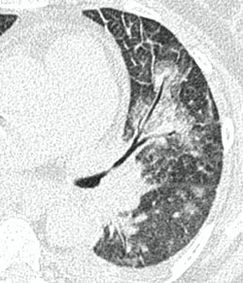

Методы лучевой диагностики применяют для выявления COVID-19 пневмоний, их осложнений, дифференциальной диагностики с другими заболеваниями легких, а также для определения степени выраженности и динамики изменений, оценки эффективности проводимой терапии.

КТ имеет высокую чувствительность в выявлении изменений в легких, характерных для COVID-19. Применение КТ целесообразно для первичной оценки состояния ОГК у пациентов с тяжелыми прогрессирующими формами заболевания, а также для дифференциальной диагностики выявленных изменений и оценки динамики процесса. КТ позволяет выявить характерные изменения в легких у пациентов с COVID-19 еще до появления положительных лабораторных тестов на инфекцию с помощью МАНК. В то же время, КТ выявляет изменения легких у значительного числа пациентов с бессимптомной и легкой формами заболевания, которым не требуется госпитализация. Результаты КТ в этих случаях не влияют на тактику лечения и прогноз заболевания при наличии лабораторного подтверждения COVID-19. Поэтому массовое применение КТ для скрининга асимптомных и легких форм болезни не рекомендуется.

15. Рекомендации по формированию описаний и оценке изменений в легких и ОГК при имеющейся/подозреваемой пневмонии COVID-19 представлены в Приложении 1.